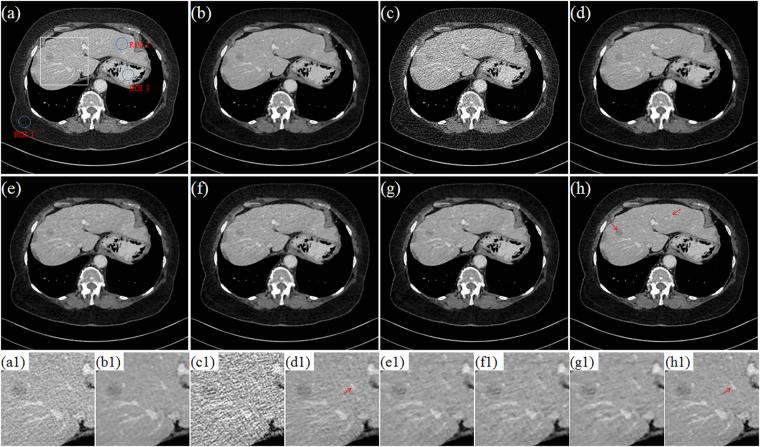

X-ray computed tomography (CT) has been widely used to provide patient-specific anatomical information in the forms of tissue attenuation. However, the cumulative radiation induced in CT scan has raised extensive concerns in recently years. How to maintain reconstruction image quality is a major challenge for low-dose CT (LDCT) imaging. Generally, LDCT imaging can be greatly improved by incorporating prior knowledge in some specific forms. A joint estimation framework termed discriminative prior-prior image constrained compressed sensing (DP-PICCS) reconstruction is proposed in this paper. This DP-PICCS algorithm utilizes discriminative prior knowledge via two feature dictionary constraints which built on atoms from the samples of tissue attenuation feature patches and noise-artifacts residual feature patches, respectively. Also, the prior image construction relies on a discriminative feature representation (DFR) processing by two feature dictionary. Its comparison to other competing methods through experiments on low-dose projections acquired from torso phantom simulation study and clinical abdomen study demonstrated that the DP-PICCS method achieved promising improvement in terms of the effectively-suppressed noise and the well-retained structures.

X 射线计算机断层扫描(CT)已广泛用于提供组织衰减形式的患者特定解剖信息。然而,近年来 CT 扫描引起的累积辐射引起了广泛关注。如何在保持重建图像质量是低剂量 CT(LDCT)成像的主要挑战。通常,可以通过以某些特定形式合并先验知识来大大改善 LDCT 成像。本文提出了一种称为鉴别先验-先验图像约束压缩感知(DP-PICCS)重建的联合估计框架。该 DP-PICCS 算法通过分别基于组织衰减特征补丁和噪声-伪影残差特征补丁的样本的原子构建的两个特征字典约束来利用鉴别先验知识。此外,通过对来自体模模拟研究和临床腹部研究的低剂量投影的实验,先验图像的构建依赖于两个特征字典的鉴别特征表示(DFR)处理。通过与其他竞争方法的比较,DP-PICCS 方法在有效抑制噪声和保留结构方面取得了有希望的改进。